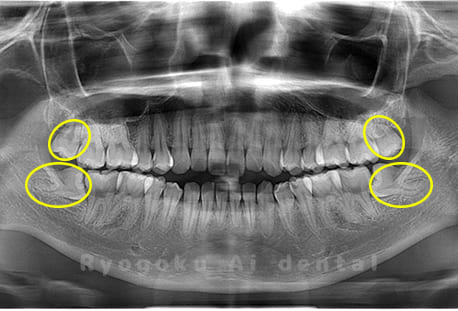

Case03

-

- 原因

- 上顎、下顎の親知らず

- 治療内容

- 上下4本の親知らずを抜歯したケースです。

<リスク・副作用>

手術後は痛み、腫れ、痺れなどの副作用が生じる場合があります。